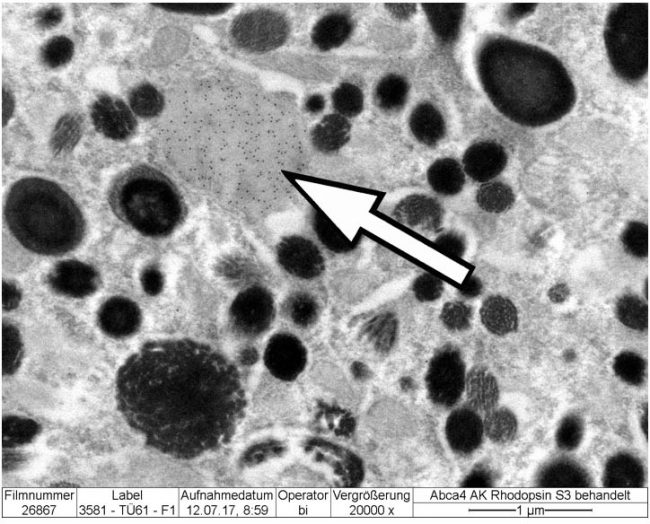

- Electron Microscope

- Electron Microscope

- Drug pigment interaction assessment

- Ocular mode of action